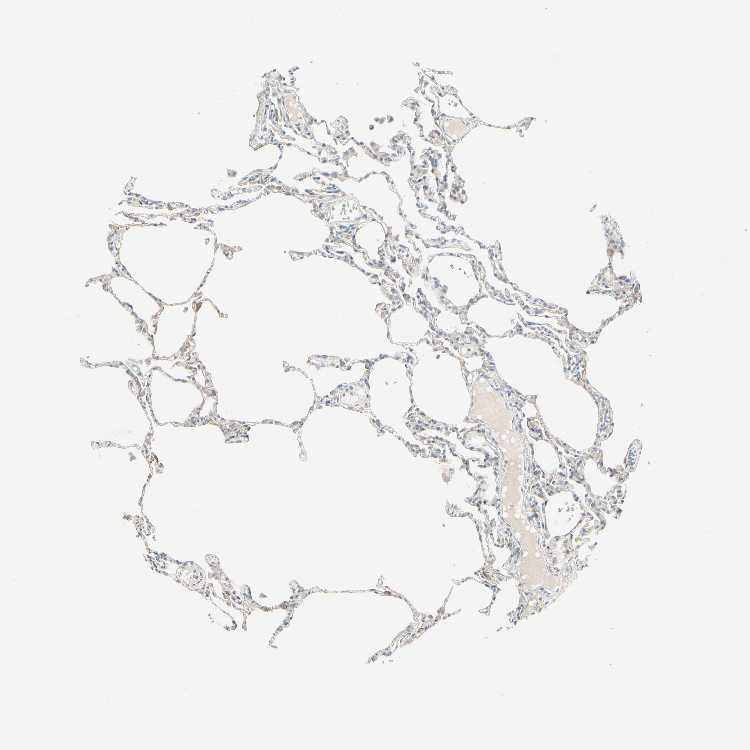

Antibody staining in the annotated cell types in the current human tissue is reported as not detected, low, medium, or high. This score is based on the staining intensity and fraction of stained cells.

Information about each individual sample is listed below, including gender, age, a tissue section image and estimated fractions of cell types. pTPM (transcripts per million) values give a quantification of the gene abundance which is comparable between different genes and samples.